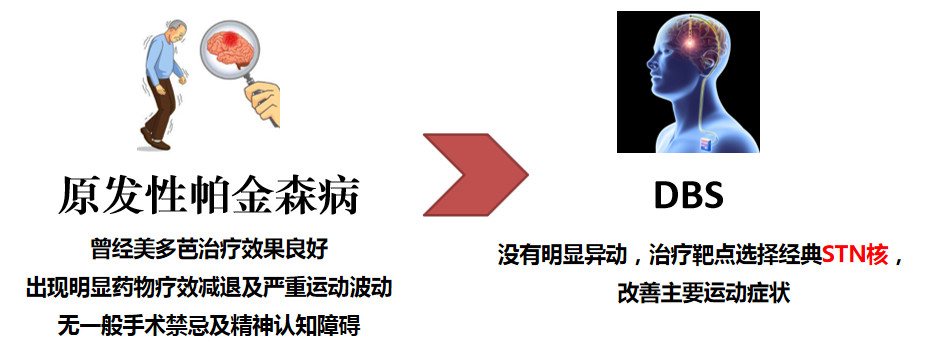

诊断及治疗